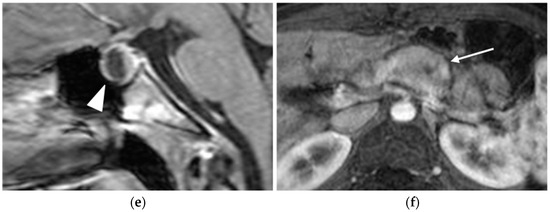

MRI

2.4. Thymic and Bronchial Neuroendocrine Tumors (Carcinoids)